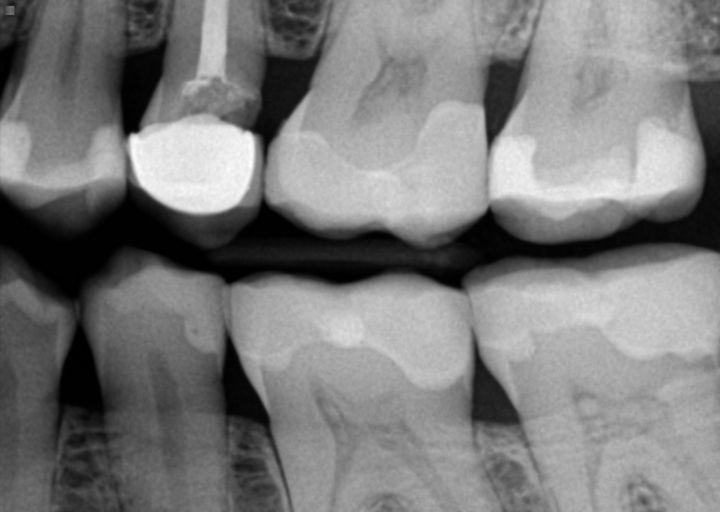

hi , i need an advise about my left lower molar tooth. I got a root canal done about 2 years ago and placed the crown couple weeks ago ( porcelain fused to high noble metal ) . Since i got this crown my tooth started to hurt when i was chewing food on it , i called my dentist and he found that crown is too high so he removed a bit of it but the problem is still existing . Now I started to feel the pain when brushing the tooth ( the gym hurts around it). also when I press with my finger the gym it hurts too. Today i went to my dentist again and informed him about the issues and he looked at it and thinks that the crown is ok only the problem is the gym and he took out a food that was in the gym around ( it was very painful and bleeding ) . Also i can't do the regular flossing because i can't get to this area with my hands its too far , so my dentist suggested me to buy a proxy brush for it . Do you think this kind of problem sounds like the gym issue or the problem is with the tooth itself and i should visit another dentist ? the last x-ray was 2 month ado and doctor sad everything is fine . before the crown was places this tooth and gym around never made any discomfort .